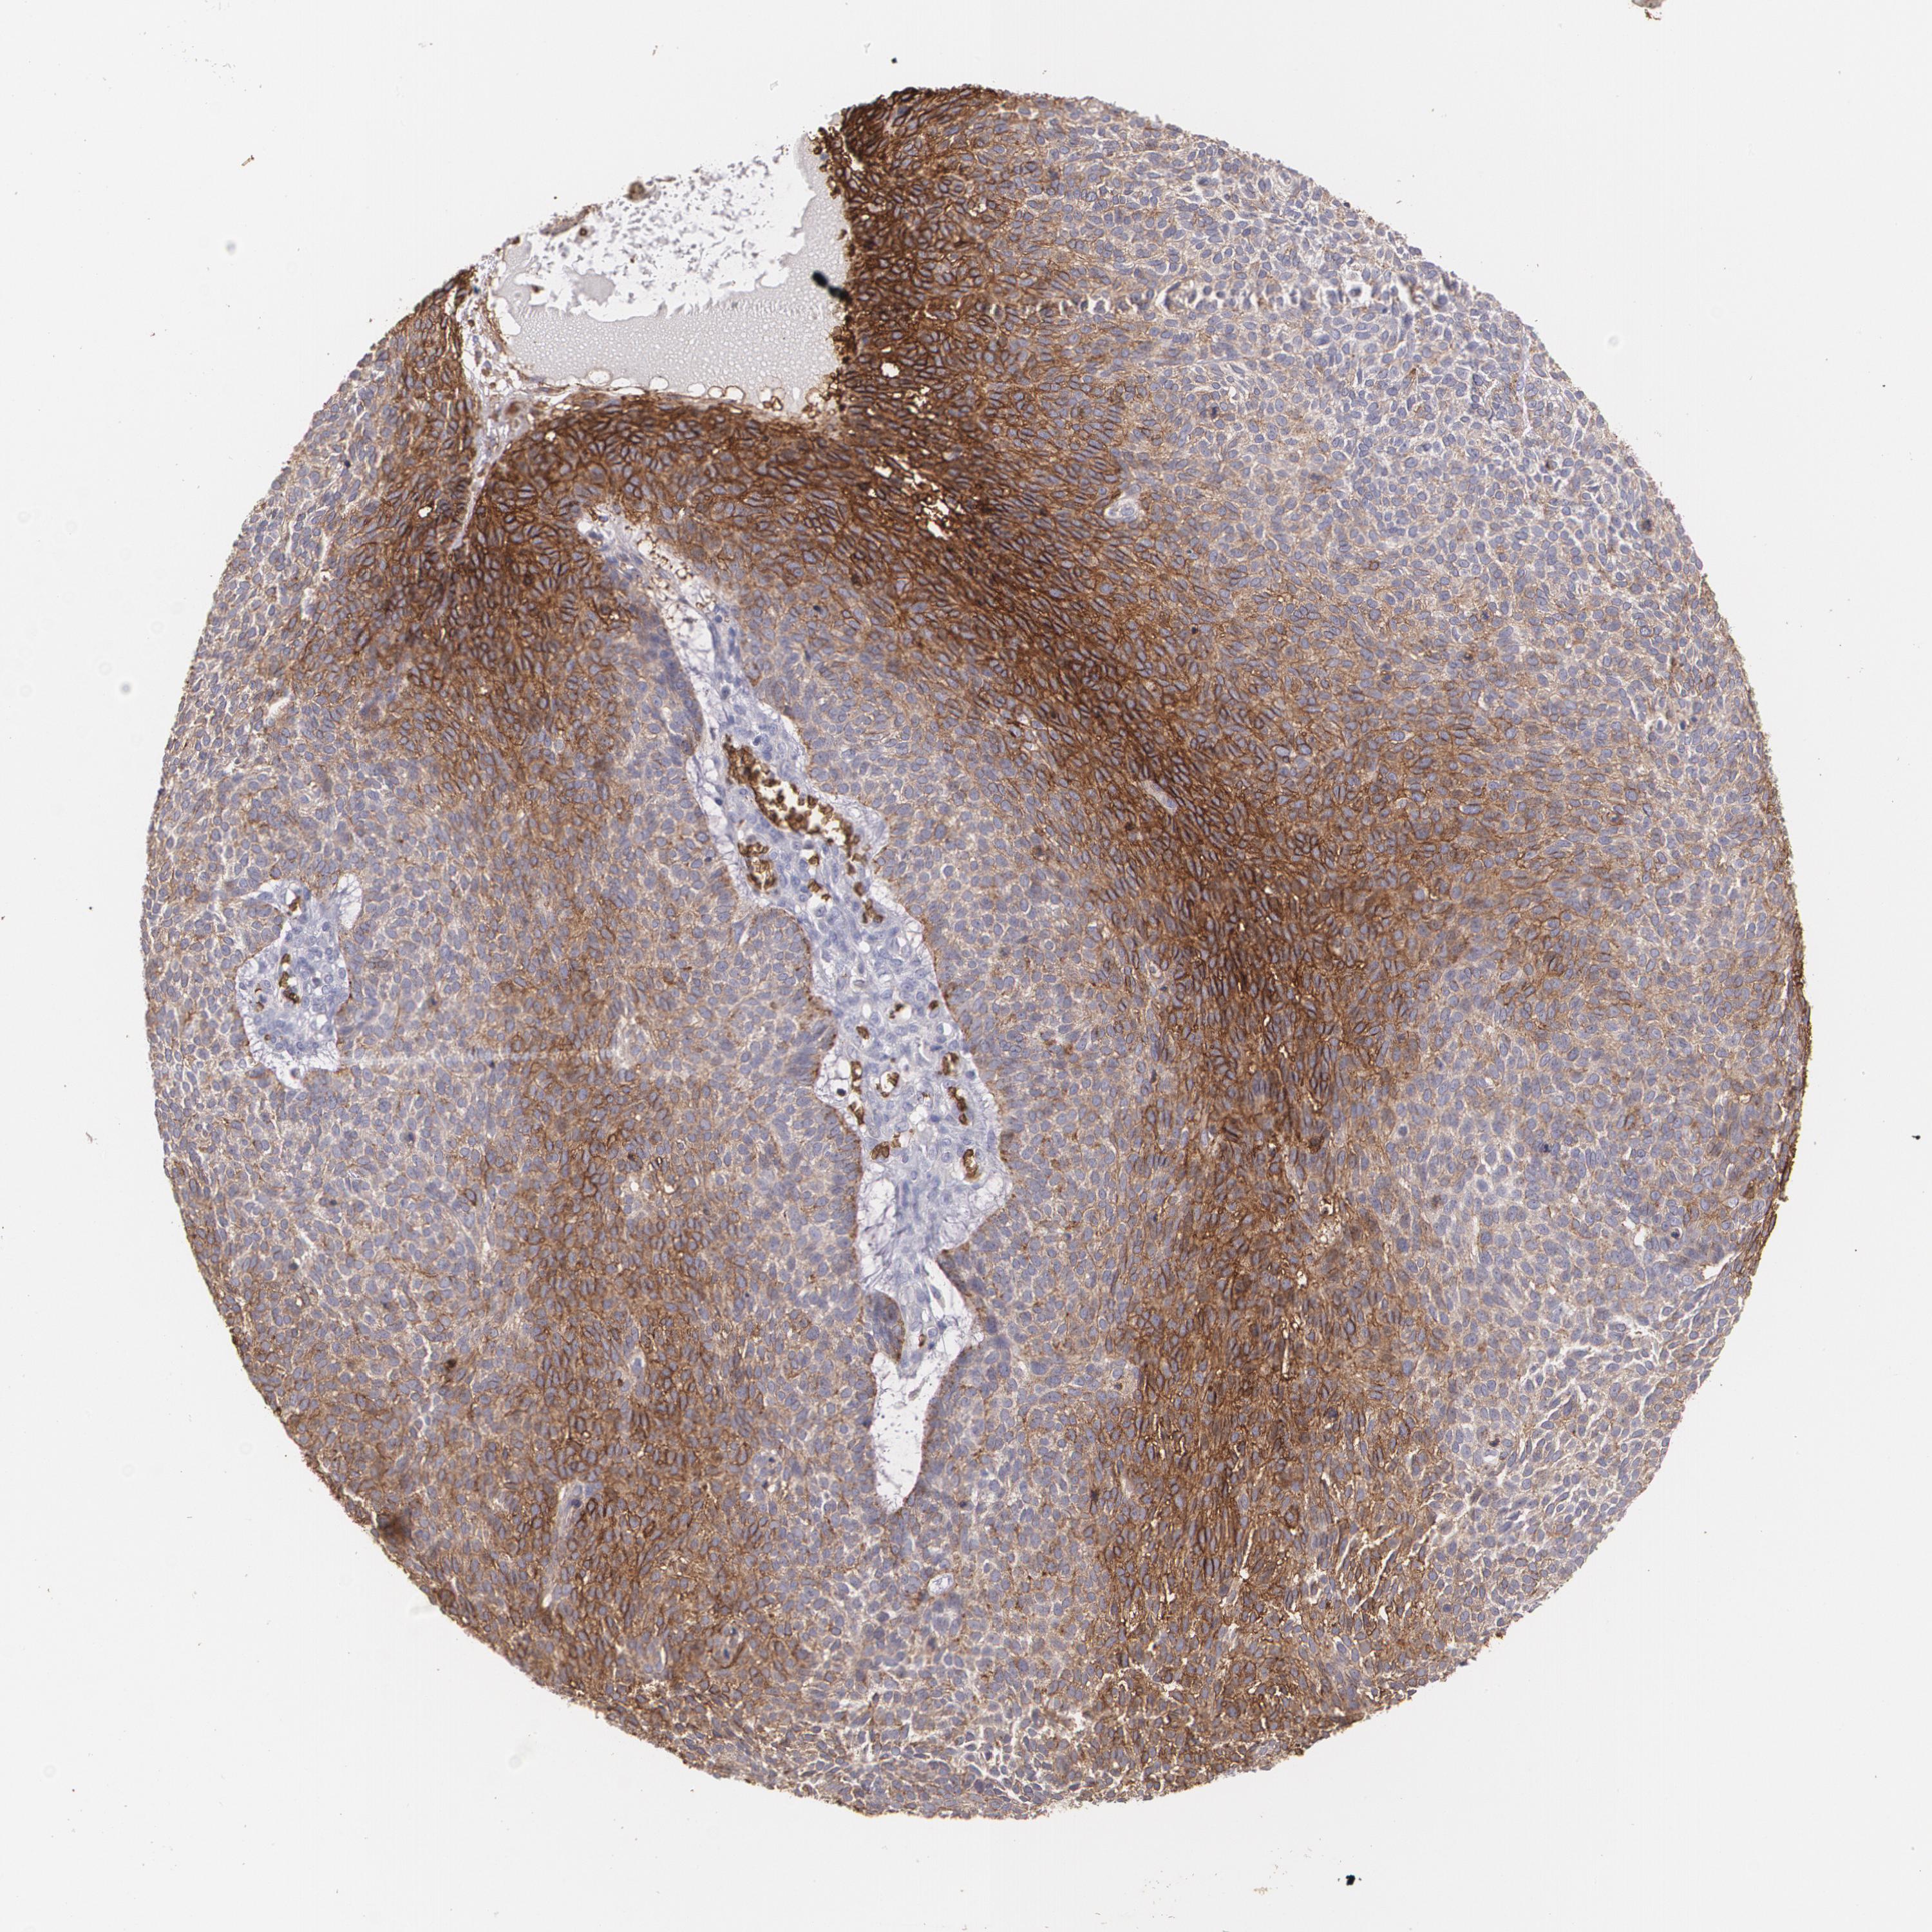

Basal cell and squamous cell cancer

SKIN CANCER - Protein expressioni

A mouse-over function shows sample information and annotation data. Click on an image to view it in a full screen mode. Samples can be filtered based on level of antibody staining by selecting one or several of the following categories: high, medium, low and not detected. The assay and annotation is described here.

Each image is clickable and will lead to virtual microscopy that enables deeper exploration of all samples and also displays staining intensity scores, fraction scores and subcellular localization as well as patient and tissue information for each sample.

Antibody CAB002759

Squamous cell carcinoma, metastatic, NOS